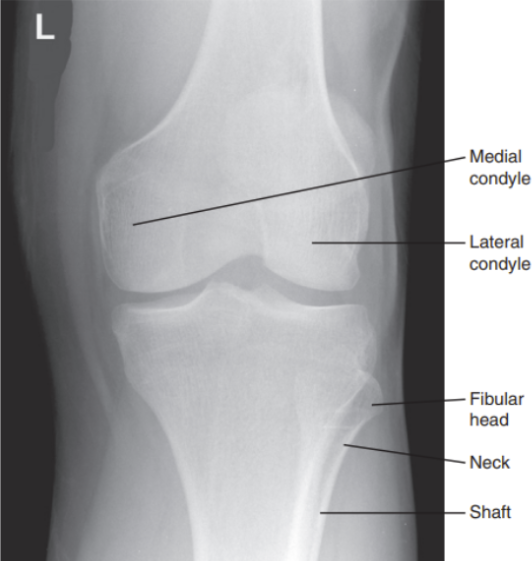

Proximal tib/fib are not superimposed

Superimposition of proximal tib/fib

Tibia superimposed with less than ¼ of fibula head

Internal rotation

Tibia superimposes more than ½ of the fibular head

Internal rotation/ under-rotated

Tibia superimposes less than ½ of the fibular head

External rotation/ under-rotated

Less than ½ of the fibula head is superimposing with tibia

More than ½ of the fibula head is superimposing with tibia

External rotation

What are the issues with this AP knee?

Intercondylar fossa is shown

Knee is flexed and not straight